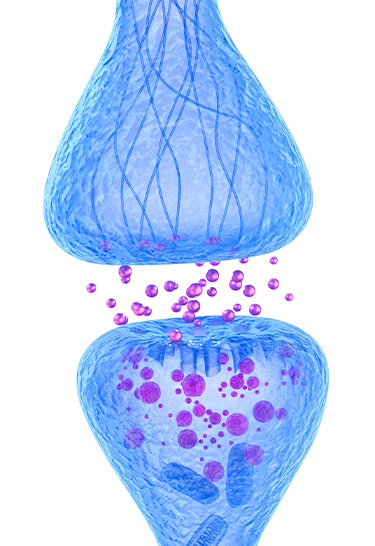

Citicoline is a molecule similar in structure to Vitamin B. It's made in your liver, then sent to your brain, where it combines with oxygen to form acetylcholine.

It's half the building blocks of your Mental Powerlines.

Now, as long as you're breathing, you're getting enough oxygen to make acetylcholine.

Low levels of acetylcholine are caused by…

Low levels of citicoline.

Which solves the whole problem, because…

…your brain can create enough acetylcholine.

It repairs your Mental Powerlines…

So energy can once again get from Point A to Point B inside your brain.